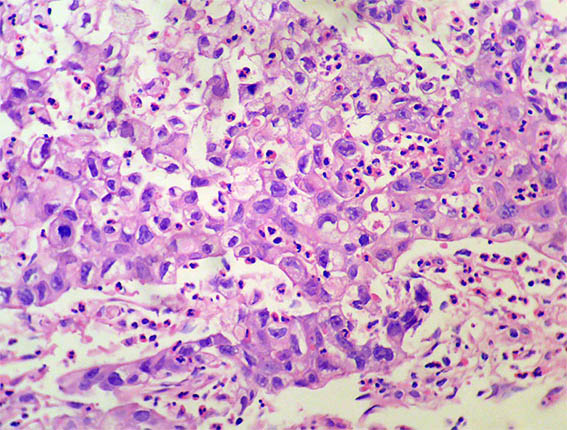

Figura 4. H&E, X200.